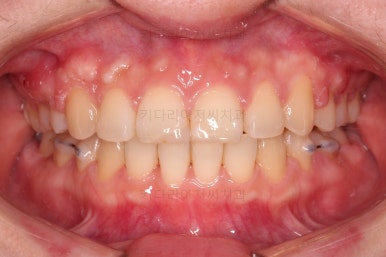

부산연산동교정치과 치료 종료 시의 모습이에요.

삐뚤한 치열도 가지런해졌고 2급 부정교합도 정상교합으로 맞춰졌어요.

튀어나와있던 앞니도 좋아졌고, 과개교합도 개선이 되었어요.

옆라인도 좋아졌고 입술을 다무는 느낌이 굉장히 편안해져서 입이 많이 들어간 건 아닌듯하지만 얼굴모습은 매우 좋아졌어요.

이처럼 얼굴모습을 좋아지게 하는건 입을 무작정 많이 넣는게 다가 아니에요.

전후 사진을 비교해 보겠습니다.

전후 사진을 나란히 놓고 비교해 보면 굉장히 많이 좋아진 것을 볼 수 있으실거에요.

웃을 때의 치아의 위치를 보면 뒤로 들어간 것을 볼 수 있고, 이 영향으로 입매도 매우 예뻐졌고 편안해졌어요.

교합이나 치아배열의 모습도 좋아졌고요.

특히 관리가 힘들어 썩었던 치아도 충치치료 없이 발치교정할 수 있었고요.

남아있는 충치는 치료해야 되지만 교정치료는 잘 마무리 되었어요.